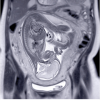

| 9:15 | Vasa Previa: Diagnosis and Management | Juan M. Gonzalez Velez, MD, PhD | ||